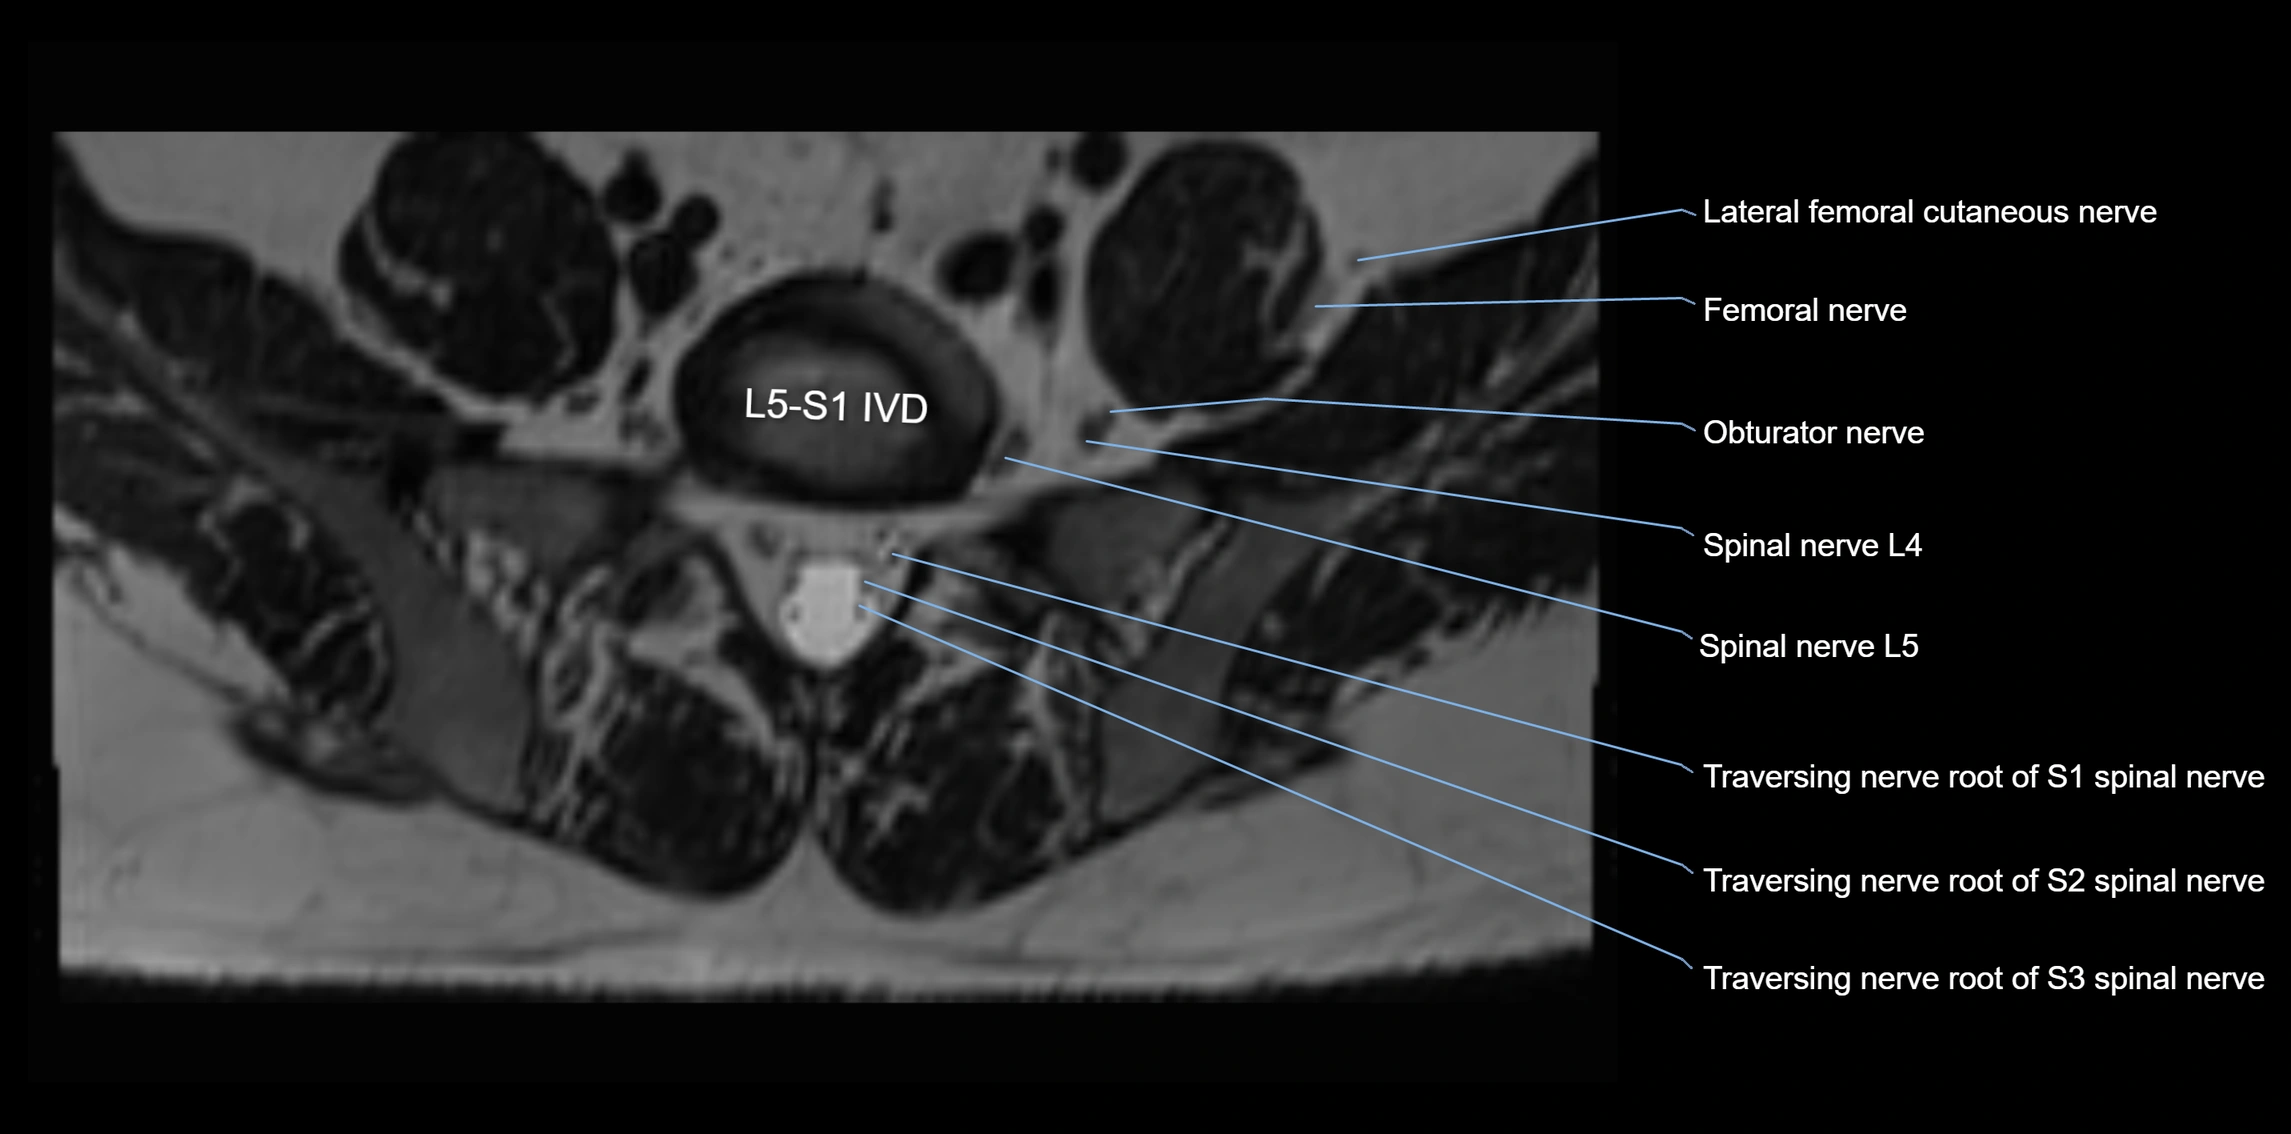

MRI Appearance

T1-weighted images:

• Nerve appears as a very thin low-to-intermediate signal intensity structure

• Surrounded by bright fat, aiding visualization

T2-weighted images:

• Nerve shows intermediate to mildly hyperintense signal compared to muscle

• Pathological involvement appears brighter

STIR (Short Tau Inversion Recovery):

• Normal nerve appears dark

• Inflamed or entrapped nerve appears bright hyperintense

T1 Fat-Sat Post-Contrast:

• Normal nerve enhances minimally

• Pathologic nerve (neuritis, entrapment, tumor infiltration) shows focal or diffuse enhancement

3D T2 SPACE / CISS:

• Nerve appears intermediate to mildly hyperintense compared to muscle

• Surrounded by bright fat or CSF, improving visualization

• Best sequence for mapping small pelvic nerves such as the anococcygeal